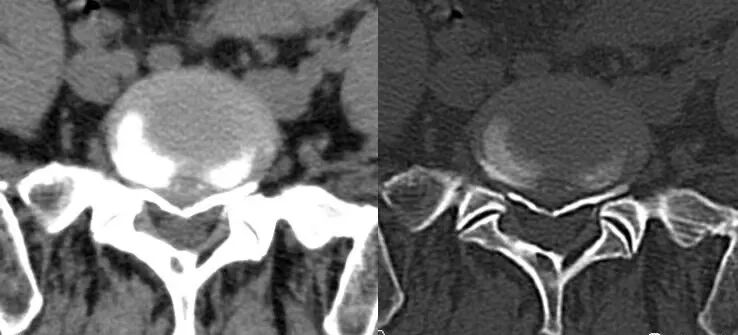

二、CT:也是利用x光扫描,可以围绕人体360度无死角的进行扫描。

(椎间盘突出,后纵韧带骨化)

优点:CT扫描能观察到横断面的细节,能了解腰椎的骨质情况、椎间盘突出和硬膜囊神经根的关系,椎间关节之间的情况等;可以做到薄层几百幅图像能更好的看清细小的病变,特别是微小的骨折;在扫描结束后可以通过影像后处理的方法,把腰椎图像重建成矢状位或冠状位,可从多个平面的不同角度去观察腰椎的影像情况。

缺点:辐射量相比DR成倍增加,而且还是不能很好的显示软组织结构、韧带及椎管内情况等。